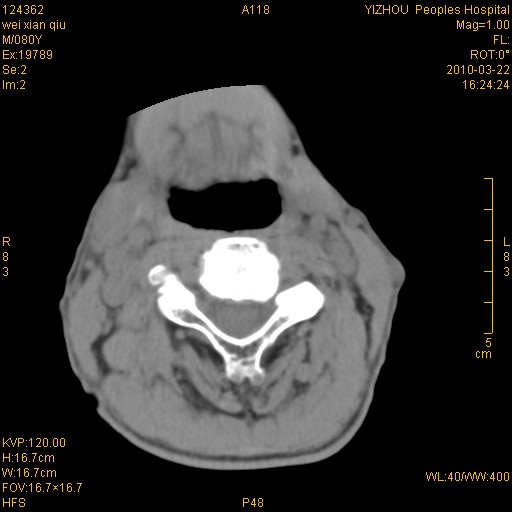

标题: CT25263:喉部占位?

男,80岁.声嘶三月余.

右侧喉癌可能性大,建议喉镜检查

考虑喉癌;建议行喉镜检查(活检)进一步明确诊断。